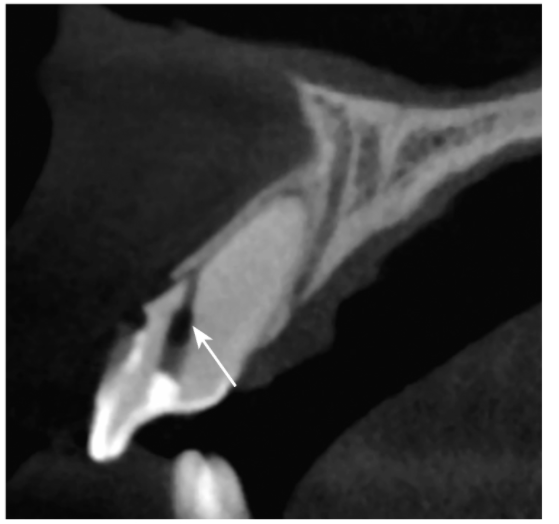

图2-2-6 B1弥漫性钙化伴侧穿

CBCT矢状位示B1弥散性钙化,自舌侧窝至唇侧牙颈部见侧穿(白色箭头)